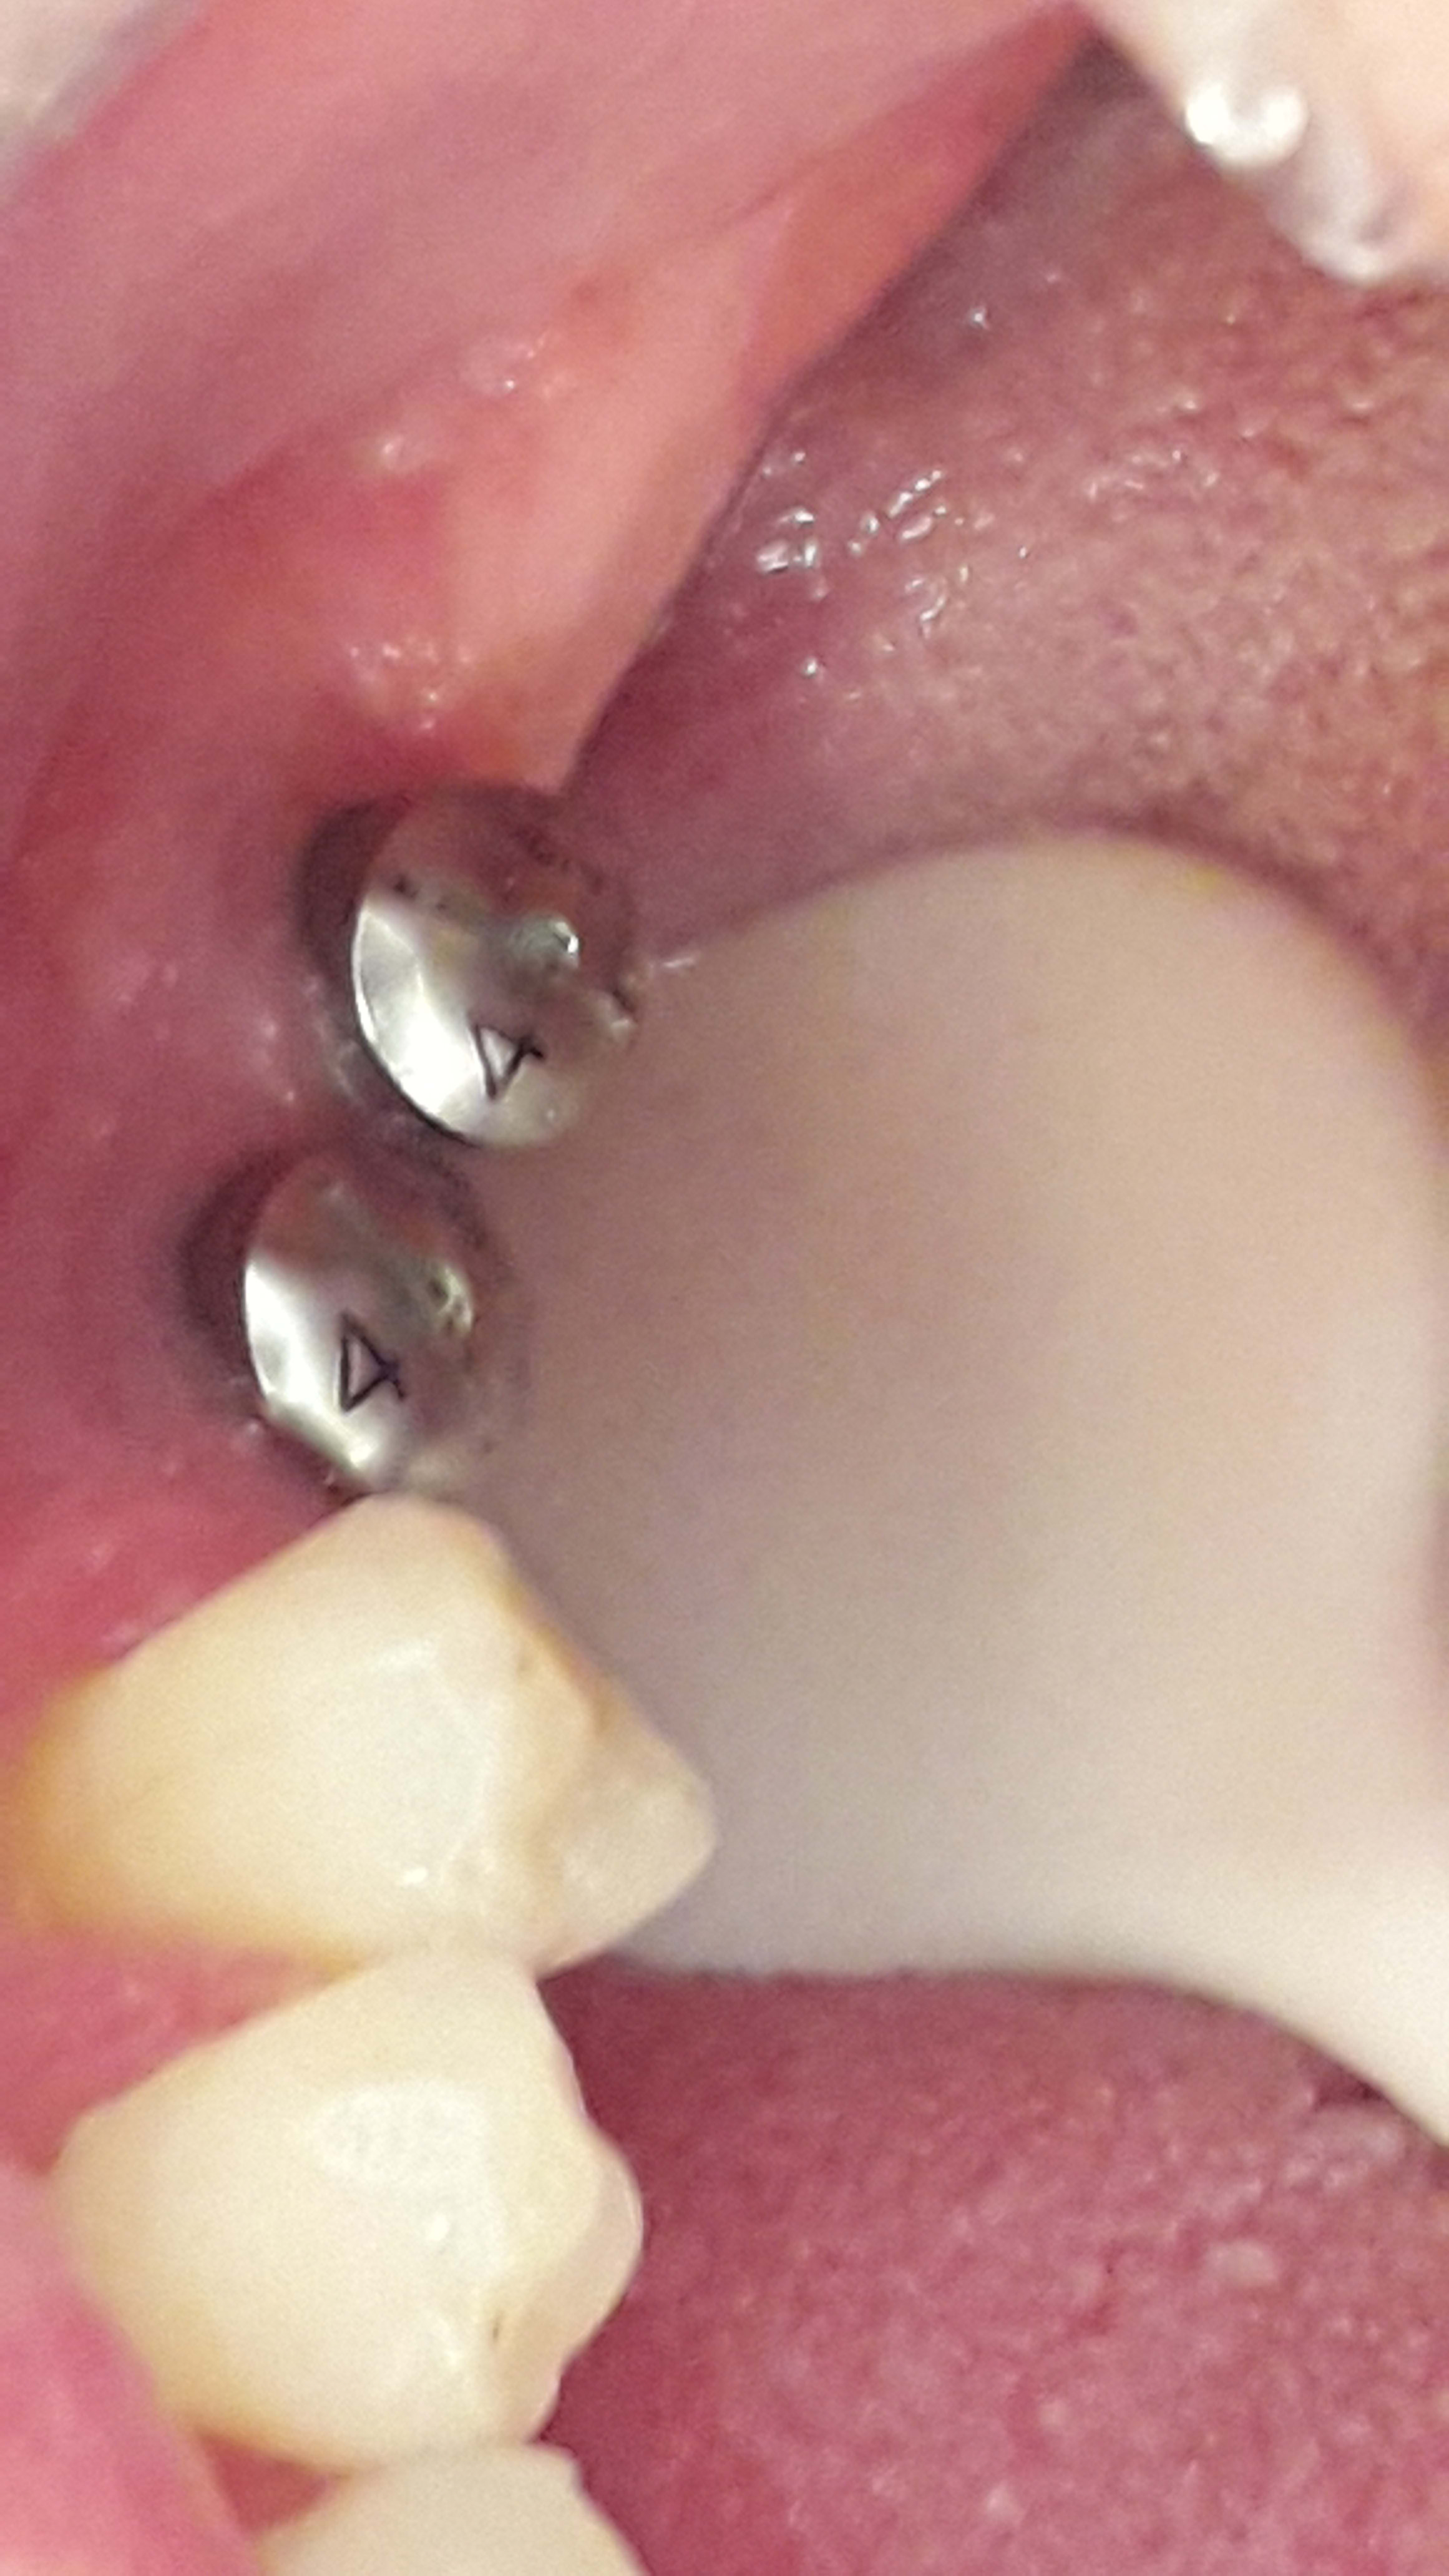

Un nouveau patient est venu au cabinet afin que je fasse les coiffes sur ses implants posés il y a 2 ou 3 ans mais il n a pas de fiche de traçabilité et ne se rappelle plus de qui les lui a posé.

J ai fait des photos... si jamais quelqu' un reconnaît la marque... Ce serait génial.!

Biomet 3i osseotite

et puis, je dis çà, je dis rien...mais çà va être "chaud patate" pour placer les 2 transferts côte à côte....

C'est ce que je me suis dit aussi .  Ceci dit les transferts biomet sont assez fins et pas trop grands .

Ou alors y a peut-être moyen de mettre des piliers Encode si c'est pas possible avec la technique classique ?